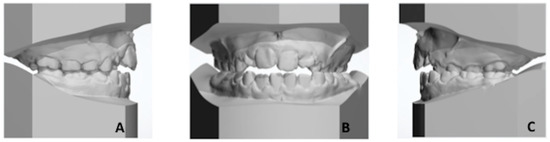

2.1. Patient’s Clinical Characteristics

2.4. Diagnosis and Treatment Plan